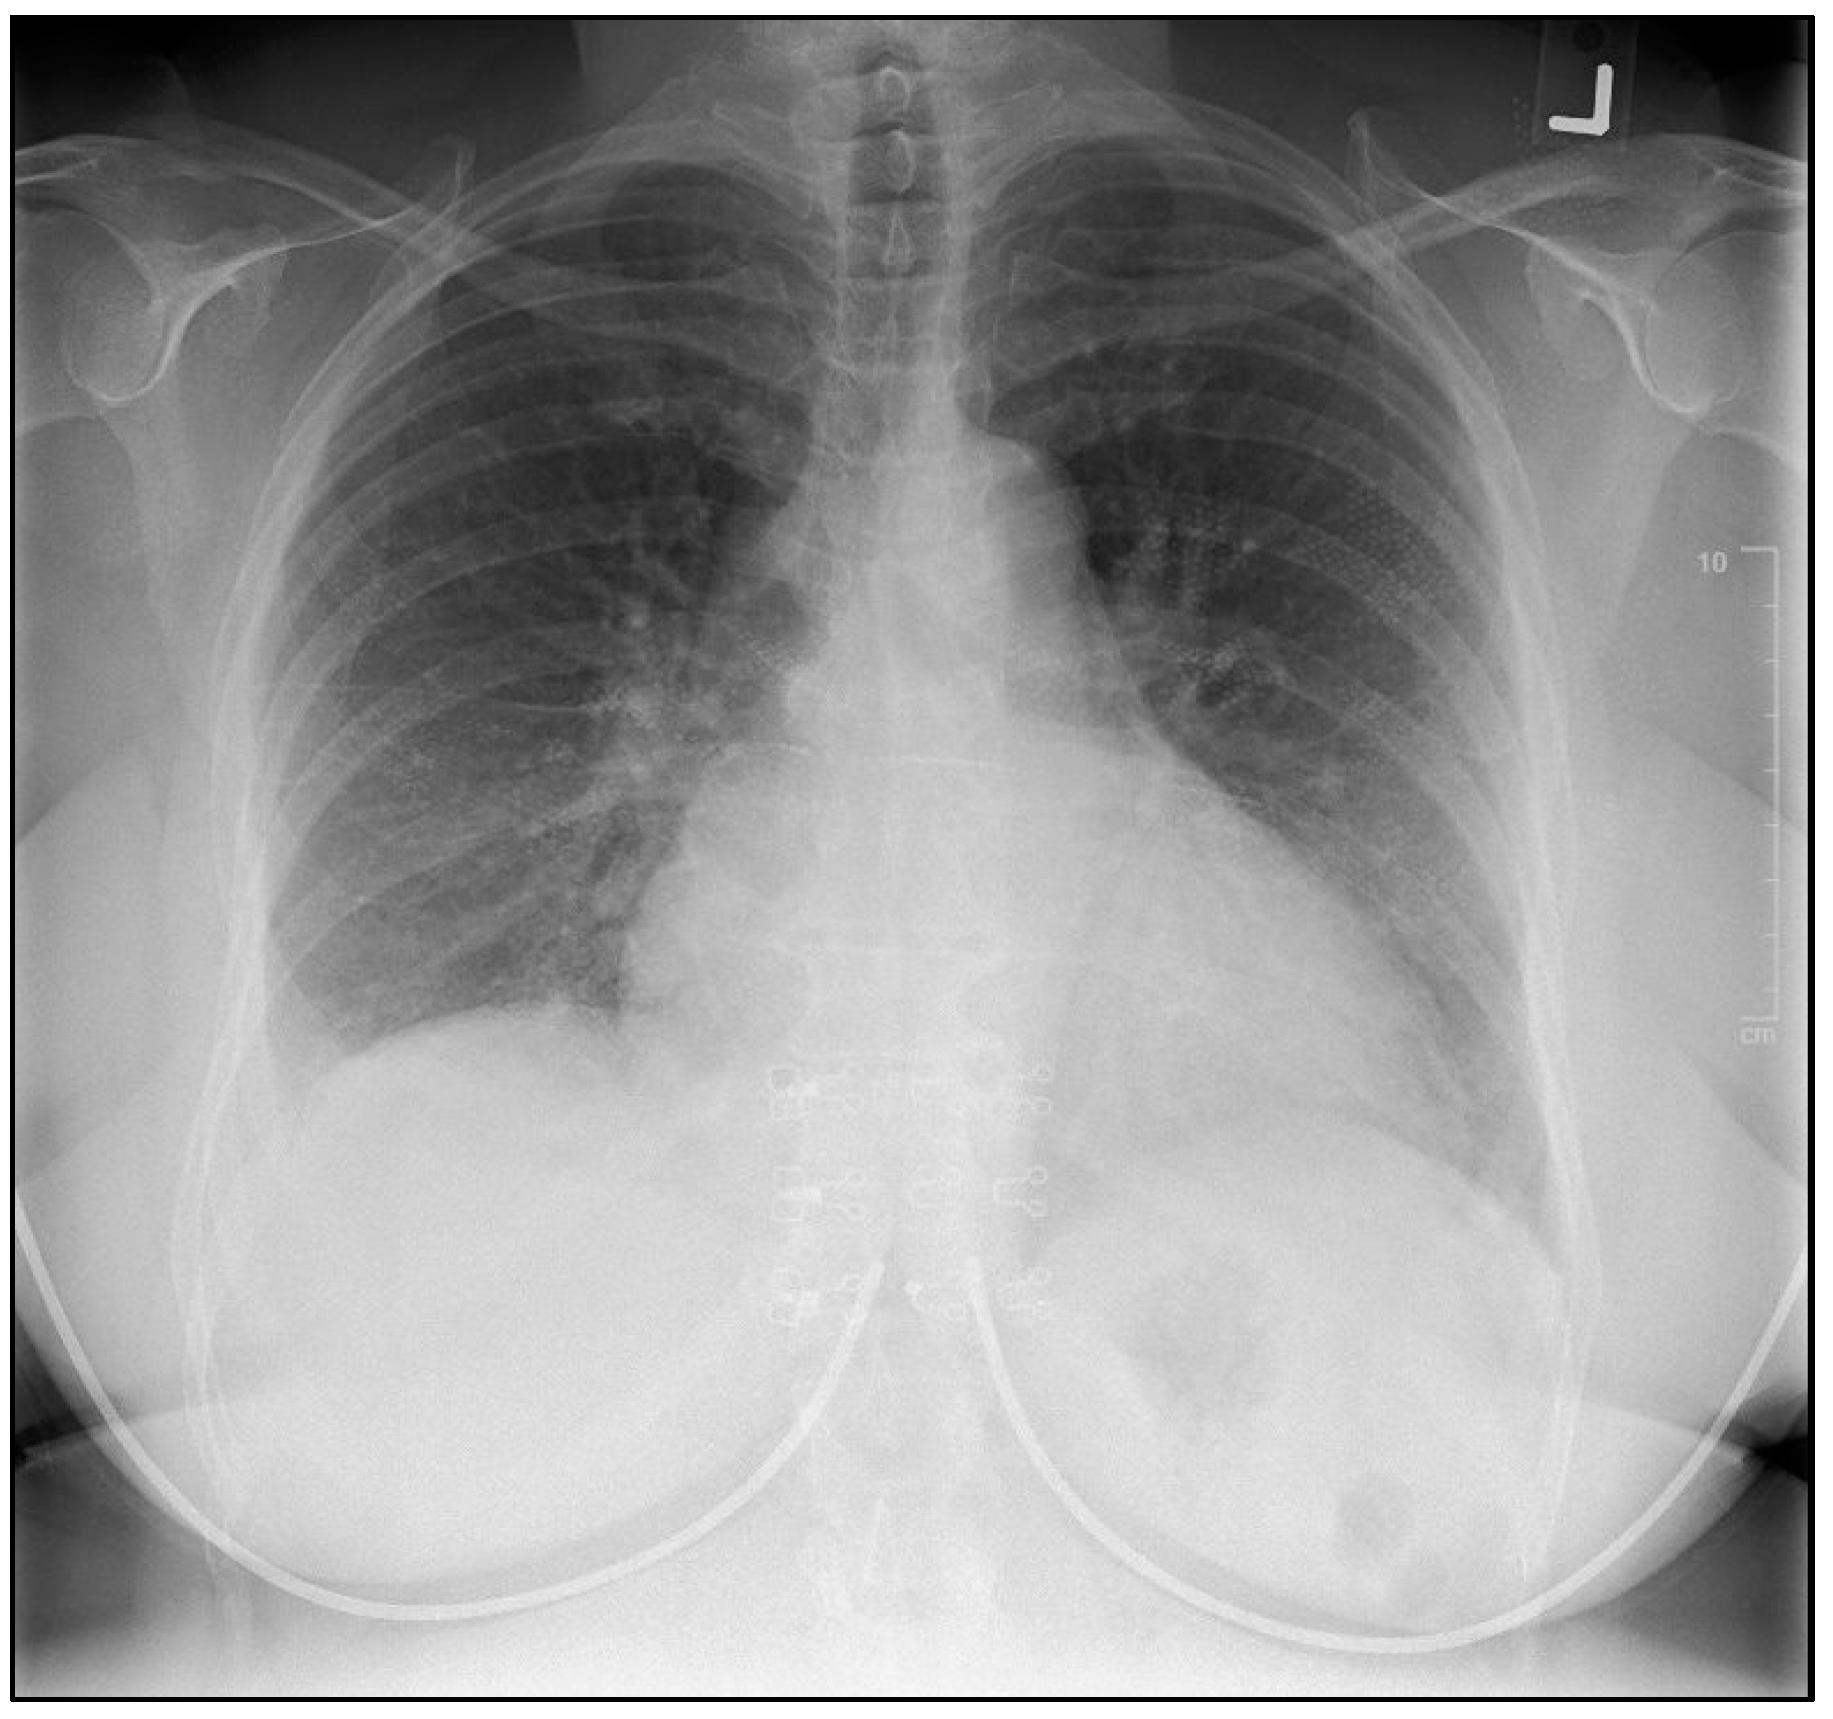

2. Case Presentation

2.1. Investigations